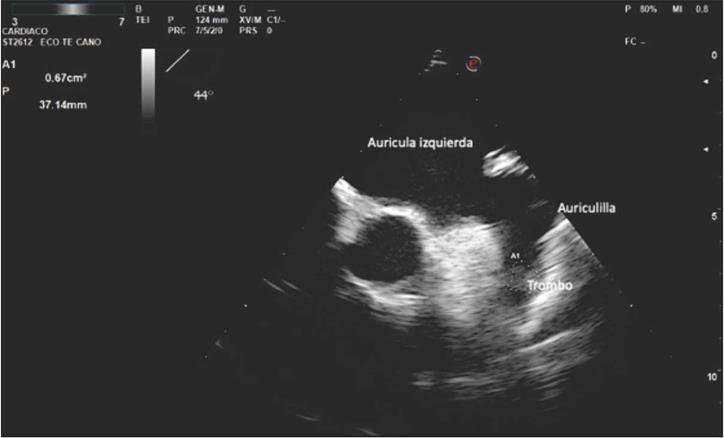

Durante el seguimiento se le realizaron controles ecocardiográficos que demostraron remodelación inversa de la aurícula izquierda con normalización del diámetro y volumen. Con un riesgo embólico calculado por la escala CHA2DS2-VASc de 1 y ausencia de síntomas, se decidió en consenso con el paciente la suspensión del medicamento antiarrítmico y el anticoagulante. Se manejó con ASA 100 mg/día, succinato de metoprolol 50 mg/día. Luego de ocho meses de la interrogación del monitor de eventos implantable (durante la pandemia de COVID SARS 2), consultó por un cuadro de instauración súbita durante su actividad laboral consistente en hemiparesia derecha y afasia. Se documentó hipertensión arterial severa al ingreso al servicio de urgencias, además, accidente cerebrovascular isquémico en las ramas superior e inferior de la arteria cerebral media bilateral y anterior derecha aguda, con signos de transformación hemorrágica en la resonancia magnética nuclear cerebral (Figura 2). En la interrogación del monitor de eventos implantable se documentó un aumento en la carga de fibrilación auricular en los últimos 15 días previos al evento isquémico (Figura 3). Se le realizó un ecocardiograma transesofágico a las 48 horas de el evento, el cual demostró la presencia de un trombo en la auriculilla izquierda (Figura 4). Estudios complementarios realizados no demostraron enfermedad carotídea o serología positiva para enfermedades protrombóticas, incluyendo infección por SARS COVID 2.